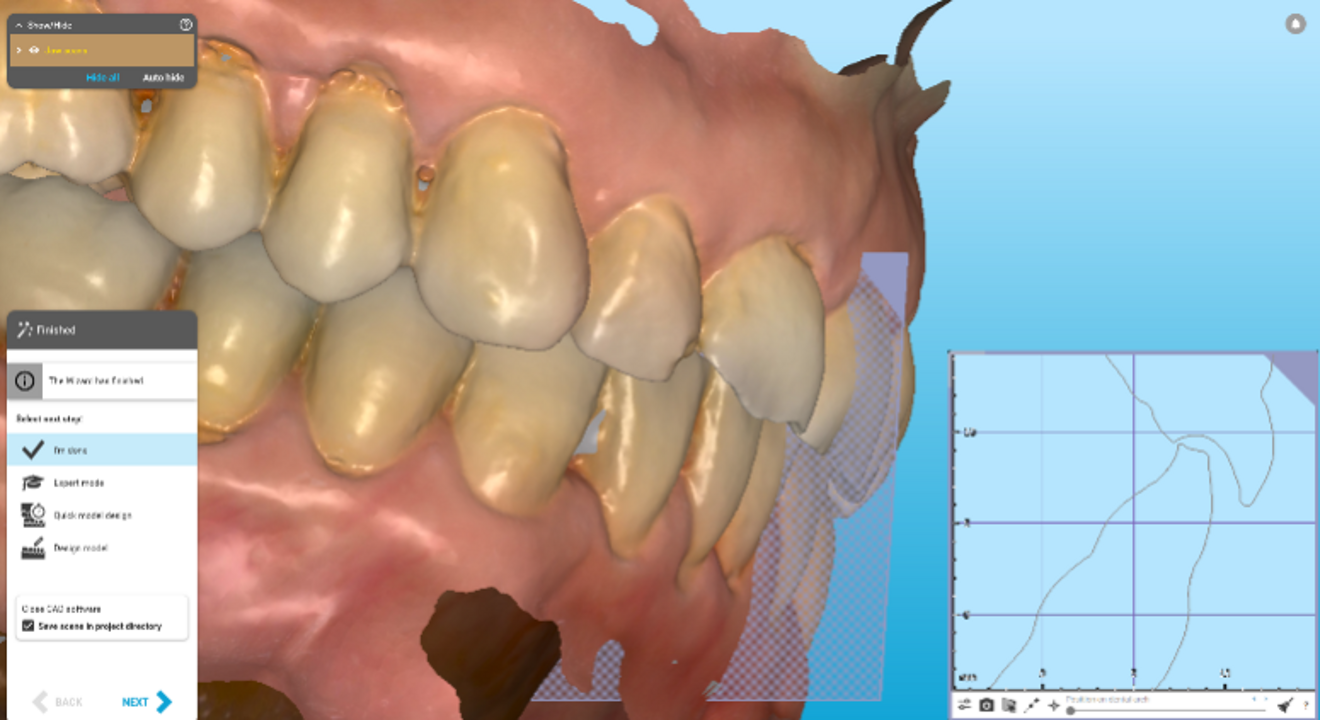

Figs. 3a & b: Side-by-side lingual view of the pre- (a) and post-alignment ClinCheck images (b) with restorative overlay displaying orthodontic space creation for the restorative and prosthodontic phase of treatment.